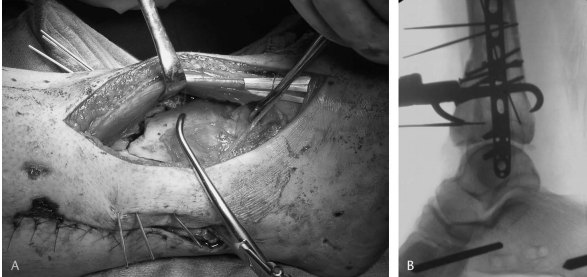

有多种技术可用于控制和复位后外侧关节骨块,包括使用从前向后直接置入前侧松质表面的操控杆,或使用置于腓骨后方并卡在胫骨后外侧的大型尖端复位钳(图 6)。或者,可以将尖端复位钳的一个尖或一个肩钩小心地穿过下胫腓联合,以勾住后外侧骨块的近端延伸部分。最准确的复位可能是通过一个单独的后侧入路到达后侧骨块。然而,这可能需要在患者俯卧位进行单独的手术。无论如何,后外侧骨块的复位决定了剩余关节骨块以及整个关节的冠状面和矢状面复位。因此,准确恢复此骨块至关重要。常见的需要进一步复位的后外侧骨块持续性旋转异常是背屈。

图 6. 通过一个小的后外侧切口 (A) 放置大型尖端复位钳,以促进后外侧关节骨块与完整胫骨 (B) 的复位。